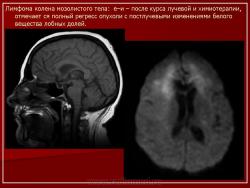

ГМ. Онк. Лимфомы головного мозга. Набор изображений. +

Лимфомы головного мозга.